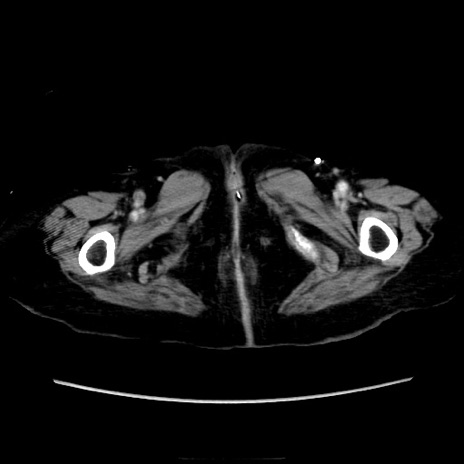

症例40(横断像)

横断像